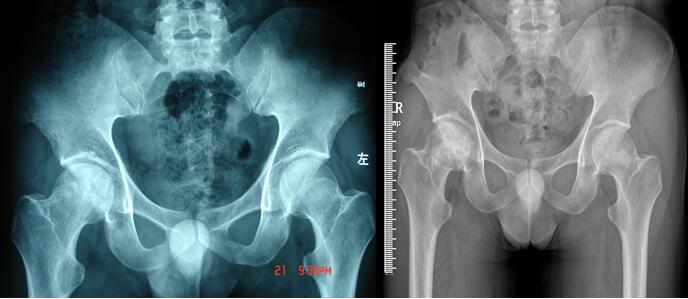

双侧股骨头坏死患者在我科行植骨保头手术治疗,一年后完全康复,现术后13年,双髋功能正常。图示为术前及术后3年的X光片。